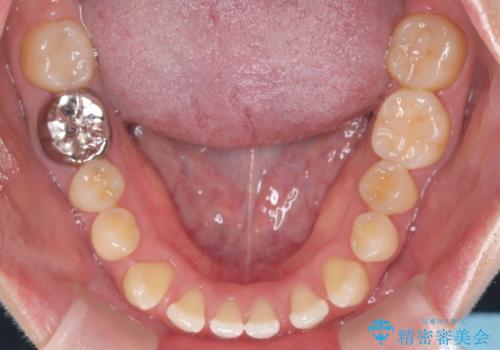

すきっ歯・切端咬合・空隙歯列|インビザラインで11ヵ月で治療完了

- すきっ歯と切端咬合(上下の前歯が先端で当たるかみ合わせ)を主訴にご来院された患者様です。

矯正検査を行った結果、非抜歯でインビザラインによる治療が可能と判断し、マウスピース矯正で改善を行いました。

11ヵ月で矯正治療が終了し、前歯の隙間も改善、見た目とかみ合わせも良好な状態となり、患者様にも大変ご満足いただけました。